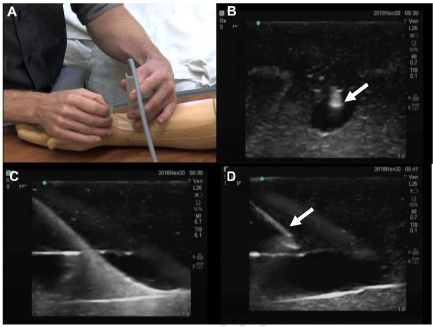

Die ultraschallgestützte Punktion der Radialarterie dient nicht nur der Schonung des Gefäßes, sondern unterstützt auch die gezielte Auswahl einer optimalen Punktionsstelle. Ein strukturierter Ansatz wie die AIM-Methode (Arterial Introduction Method) kann hierbei wertvolle Dienste leisten.

Im Rahmen dieser Methode wird die Radialarterie mithilfe eines hochauflösenden Ultraschallgeräts in einem Bereich etwa 4 cm proximal des Handgelenks untersucht – einer Region, die in der Literatur gelegentlich als „Chi“ (Cheok) bezeichnet wird. In diesem Abschnitt ist die Arterie in der Regel größer kalibriert, tiefer gelegen und weniger durch Gelenkbewegungen beeinflusst. 4

Mehrere Autoren empfehlen bei der ultraschallgestützten Kanülierung der Radialarterie die Verwendung eines longitudinalen Zugangs (in-plane-Technik) mit einem Einstichwinkel zwischen 30° und 45°. Besonders vorteilhaft ist jedoch ein flacherer Winkel zwischen 15° und 30°, da dieser die subkutane Katheterstrecke verlängert, bevor das Gefäß lumeniert wird. Dies führt zu einer höheren mechanischen Stabilität des Katheters und reduziert das Risiko für Dislokationen, mechanische Irritationen sowie infektiöse Komplikationen 11.